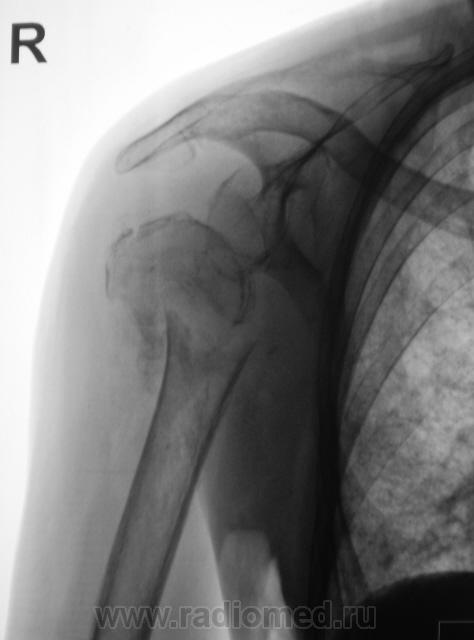

Травма. Пациентка "преклонного" возраста направлена на рентгенографию плечевого сустава.

головки плечевой кости. Вопрос только в том. будет ли этот прелом на фоне остеопороза или пат. изменённой костной ткани?

Вероятно перелом патологический, на фоне метастатического поражения. Показана рентгенография таза, черепа.

В лёгких (кусок лёгкого виден) синдром диссеминации с обеих сторон по типу карциноматоза.

очень похоже на метастаз рака почки.

Похоже, и на метастаз...